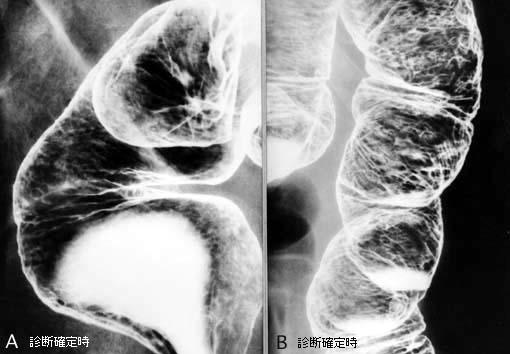

식도암과 위암을 동반한 Cronkhite-Canada증후군

[Image-ID:2205]

질환(병리주체)의 분류

종양양 병변/Cronkhite-Canada증후군

부위(장기별)

대장/2구역 이상의 대장에 걸치는 것

검사방법

X-P